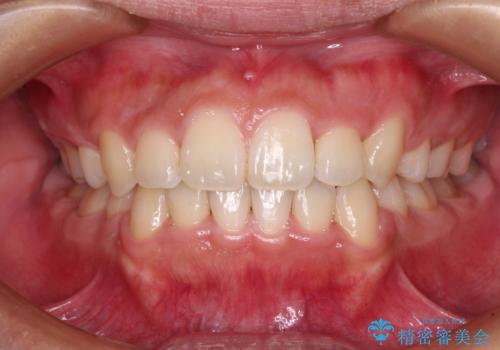

上下の前歯に隙間が空くほど上顎前歯が前に飛び出していましたが、抜歯矯正により上下前歯がぴったりと付くほど口元を引っ込めることができました。